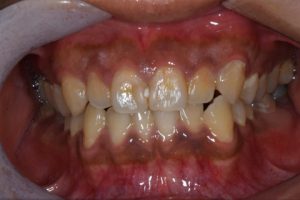

前歯が黒っぽいのが気になる、

悪いところは全部治したい

年齢 54代女性

主訴 歯をきれいにしたい

症例写真(治療前)

治療前:

八重歯が目立ちます。また銀歯もおおく、見た目が気になります。虫歯も散見できます。